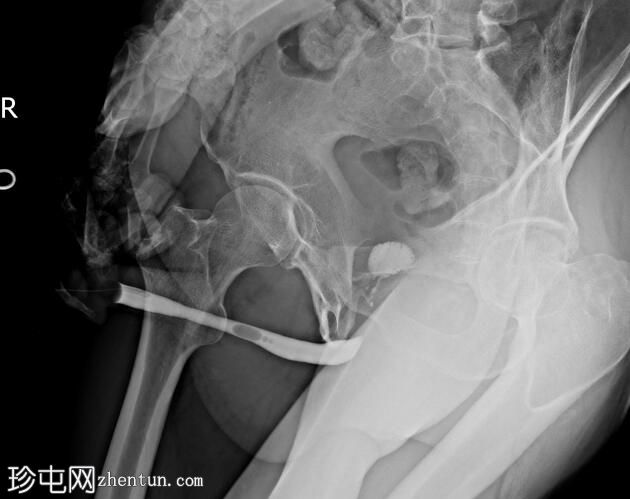

正位

斜位

前列腺部、膜部、球部及阴茎部尿道均正常。

造影剂经尿道注入,开始充盈具有肠袢特征的新膀胱。

该患者确诊为移行细胞癌后行膀胱切除术。治疗方案包括根治性膀胱切除术及新膀胱重建术。